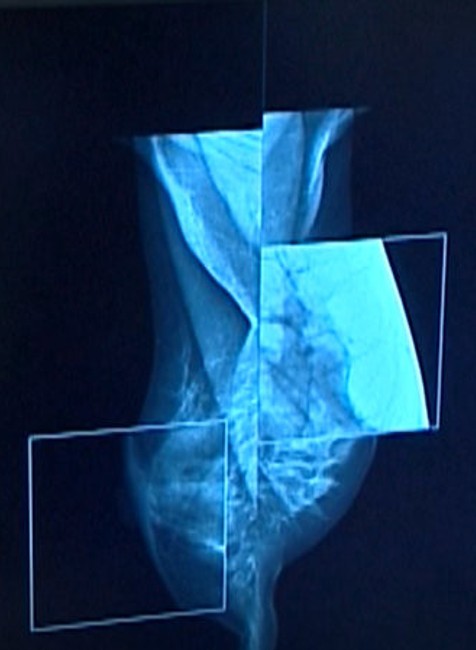

BRATISLAVA / Do redakcie TV JOJ napísal rozhorčený divák. Zarazilo ho, že najskorší termín na mamografické vyšetrenie dostala jeho dcéra až o takmer rok. Reportérka Alena Malchová zisťovala, či je to bežné a čo môžeme urobiť, ak s termínom nie sme spokojní.

Muž bol objednať svoju 42- ročnú dcéru na mamografiu 11. septembra tohto roka. Najbližší termín na vyšetrenie mu dali až na 6. augusta 2019. Informáciu sa TV JOJ priamo v ambulancii overiť nepodarilo, nikto nedvíhal telefón. Divák neupresnil v akej poisťovni je jeho dcéra ani či ide o preventívne alebo akútne vyšetrenie. Podľa oslovenej rádiologičky sa mohli stať dve veci. Buď mala nedávno podobné vyšetrenie a nechceli ju vystavovať ďalšiemu žiareniu, alebo ide o prevenciu. V takom prípade má naň nárok každá žena nad 40 rokov raz za dva roky.